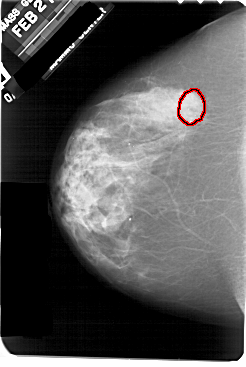

A_1930_1.LEFT_MLO

LEFT_MLO LINES 5491 PIXELS_PER_LINE 3826 BITS_PER_PIXEL 12 RESOLUTION 43.5 OVERLAY

FILE: A_1930_1.LEFT_MLO.OVERLAY

TOTAL_ABNORMALITIES 1

ABNORMALITY 1

LESION_TYPE CALCIFICATION TYPE PLEOMORPHIC DISTRIBUTION CLUSTERED

ASSESSMENT 4

SUBTLETY 3

PATHOLOGY MALIGNANT

TOTAL_OUTLINES 1

BOUNDARY